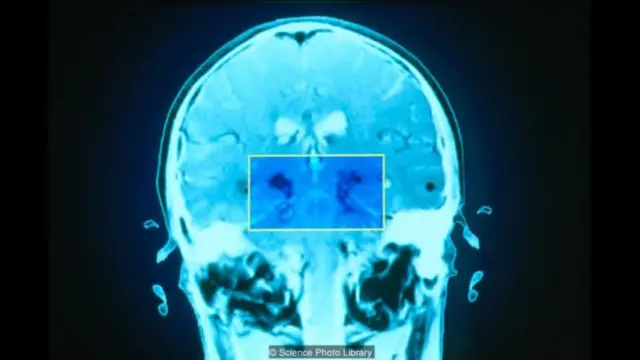

为了测量一个人的疲劳程度,科学家会请患者填写问卷,或用简单的认知测试来研究一段时间内人的表现如何变化,这是大脑疲劳的标志之一。让人困惑的是,疲劳的严重程度并不一定对应于大脑损伤的程度。但是研究说明大脑的一些区域可能与疲劳有关,包括前额叶(褶皱、树皮装表面的大脑部分,位于眼睛后方,负责有意识的、分析性思考、注意和记忆)与大脑深层区域(比如扭结的基底神经节和处理自动、本能行动的杏仁核)的连接处。“可能当某些连接被破坏后,大脑传递信息的效率降低,所以人就容易感到疲倦,”马利说。如果确实如此,那么任何脑力劳动都需要消耗一些能量,这就意味着在较少的劳累后,你储存的能量很快就会耗干。